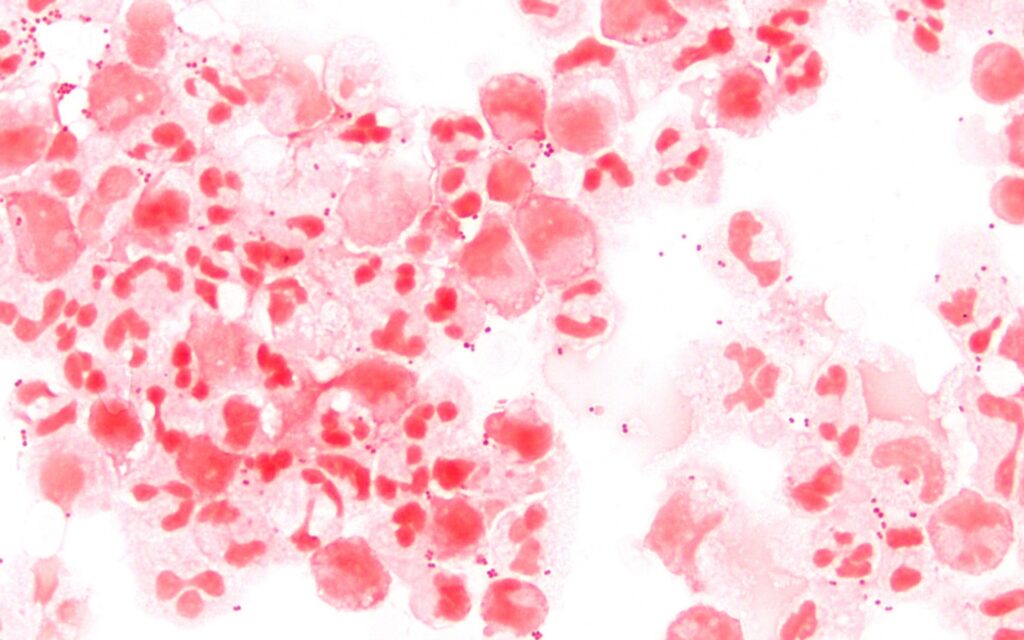

A meningite é uma inflamação das meninges, que são as membranas que protegem o sistema nervoso central. Essa condição pode ser provocada por micro-organismos, como bactérias e vírus, além de alergias a medicamentos, câncer e outras causas.

No Brasil, a meningite é considerada uma doença endêmica, com casos registrados ao longo de todo o ano. As formas bacteriana e viral da doença são as mais relevantes em termos de saúde pública, com as crianças sendo as mais afetadas. As meningites bacterianas tendem a se manifestar com maior frequência durante o outono e inverno, enquanto as virais são mais comuns na primavera e no verão.

Conforme o Ministério da Saúde, a meningite pode ser provocada por bactérias, vírus, fungos e parasitas. A transmissão ocorre quando gotículas de saliva de um indivíduo infectado entram em contato com as mucosas do nariz ou da boca de uma pessoa saudável. Isso pode acontecer através de tosse, espirros ou secreções respiratórias.